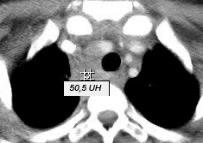

123 .MASA MEDIASTÍNICA CON ALTA DENSIDAD I INTRÍNSECA